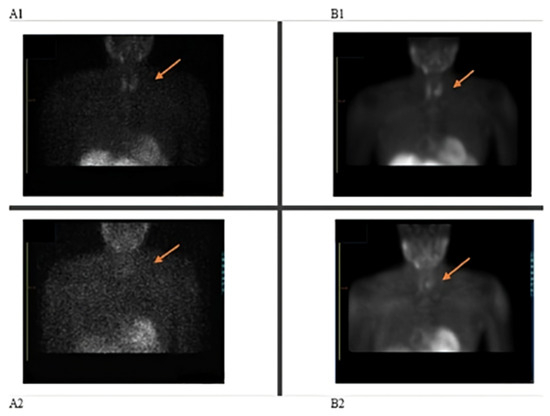

Unexpectedly, the parathyroid scan demonstrated poor tracer uptake in both the early and delayed phases, as was evidenced by compromised contrast on the acquired images. Subsequent application of attenuation correction, coupled with optimization of reconstruction parameters, led to notable improvements in image quality (Figure 1(A1,A2)). Notably, other patients who received doses from the same radiopharmaceutical kit exhibited normal uptake patterns in these tissues, suggesting a patient-specific issue rather than a problem with the radiotracer batch. Further investigation was warranted to determine the cause of the reduced uptake and to ensure accurate diagnosis. The decision was made by the Nuclear Medicine team to repeat the scan two weeks later, with an adjustment to the patient’s medication protocol. Based on the literature, a clinical decision was made for the patient to discontinue all medications for 72 h prior to the date of the rescheduled scan.

Figure 1.

Parathyroid imaging: (A1) Initial scan-early parathyroid, (A2) initial scan-late parathyroid showing non-localization of parathyroid adenoma; (B1) repeat scan-early parathyroid, (B2) repeat scan-late parathyroid showing parathyroid adenoma localization.

The repeat scan results revealed a small focus of marked tracer retention in the left inferior parathyroid bed, suggestive of a small parathyroid adenoma measuring ~0.7 × 0.6 cm (axial plane) (Figure 1(B1,B2)). Post-surgery the focus identified on the scan was removed and histologically confirmed to be a parathyroid adenoma. Comparative analysis of count statistics between the initial and repeat scans revealed reduced uptake in the initial examination, suggesting factors influencing radiopharmaceutical accumulation.